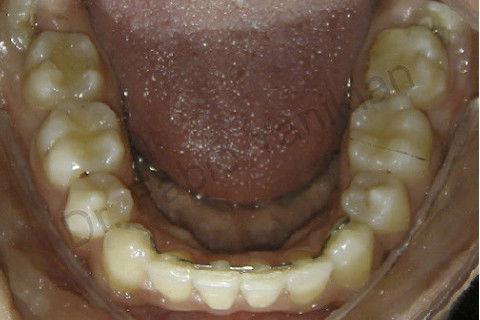

Foto oclusal inferior inicial

Foto oclusal inferior final

Paciente CL I com apinhamento superior e inferior

Evolução clínica: exo dos 4 prés, alinhamento e nivelamento, não foi necessario fazer RAS e RAI mas perda de ancoragem nos 4 quadrantes para fecar os espaços.